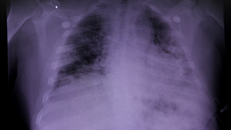

Bệnh nhân 91 hồi phục được 90% phổi

(Ngày Nay) - PGS.TS Lương Ngọc Khuê- Cục trưởng Cục Quản lý Khám chữa bệnh, Phó Trưởng Tiểu ban Điều trị- Ban Chỉ đạo quốc gia phòng chống dịch COVID-19 cho biết, sức khoẻ của nam phi công tiếp tục có những phục hồi kỳ diệu.

Ảnh minh họa